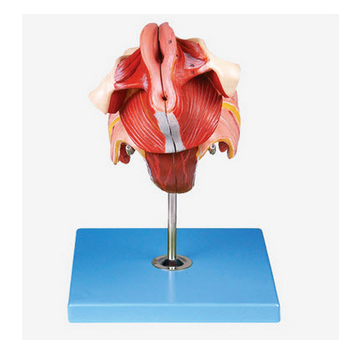

GD/A15109子宮解剖模型產品介紹:1、型號規格:GD/A151092、名 稱:子宮解剖模型3、品 牌:全科醫生4、簡 介:該模型由膀胱、子宮陰道矢切面兩個部件組成,共有15個部位指示標志。...